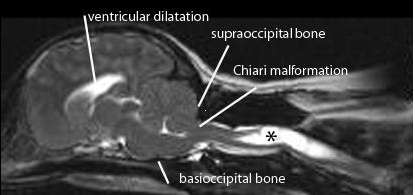

Chiari-like malformation (CM) is a condition characterised by a mismatch between the caudal fossa (skull) volume and its contents, the cerebellum and brainstem. The neural structures are displaced into the foramen magnum obstructing cerebrospinal fluid (CSF) movement. A consequence of this is syringomyelia (SM) where fluid filled cavities develop within the spinal cord (Fig 1). The primary clinical sign of CM/SM is pain, either due to obstruction of the CSF pulse pressure and/or a neuropathic pain syndrome due to damage to the spinal cord dorsal horn. This disease has also been referred to as occipital hypoplasia (Rusbridge et al 2006) and caudal occipital malformation syndrome (COMS) (Dewey et al 2005). CM/SM is sometimes erroneously confused with Arnold Chiari malformation (cerebellar and medulla herniation associated with myelomeningocoele) and occipital dysplasia (incomplete ossification of the supraoccipital bone).

FIGURE

1: Midsagittal T2 weighted MRI of the brain and upper cervical spinal

cord from 3 year old female CKCS with syringomyelia (asterisks) that first

developed signs of pain at 1.7years old. Clinical signs included shoulder

scratching at exercise and when excited. She would not tolerate her right ear to

shoulder area to be touched or groomed. She frequently screamed and her owners

were not able to exercise without her becoming distressed. She also had mild

pelvic limb weakness. She was managed with a foramen magnum decompression and

despite persistence of the syrinx, made a satisfactory post operative that was

maintained for 1.8years. Following this deterioration she was managed medically

for a further 3.8 years and is currently 7 years old.

The pathogenesis of canine CM/SM is not fully understood. An important contributory factor is thought to be that the brain is too big for the skull and early studies suggest that there is an inappropriately short skull base (basioccipital bone (Fig 1). Cavalier King Charles spaniels (CKCS) with clinical signs related to syringomyelia are more likely to have a smaller ratio of cauda fossa (i.e. back of skull) volume to total brain volume compared to unaffected CKCS (Cerda-Gonzalez et al 2006). However it is likely there are other unidentified anatomical or environmental factors. Studies comparing skull dimensions did not demonstrate a significant difference between the size of the back of the skull in CKCS with and without syringomyelia (Curruthers et al 2006, Cerda-Gonzalez et al, 2006).

DIAGNOSIS

Magnetic resonance imaging (MRI) is essential for diagnosis and determining the cause of SM (Fig 1). In the instance of CM/SM the cerebellum and medulla extend into or through the foramen magnum which is occluded with little or no CSF around the neural structures. The size of the cerebellar herniation is not correlated with severity. There is typically ventricular dilatation. SM is indicated by fluid-containing cavities within the spinal cord. The upper cervical and upper thoracic segments are typically most severely affected. Maximum syrinx width is the strongest predictor of pain, scratching behaviour and scoliosis; 95% of CKCS with a maximum syrinx width of 0.64cm or more will have associated clinical signs.